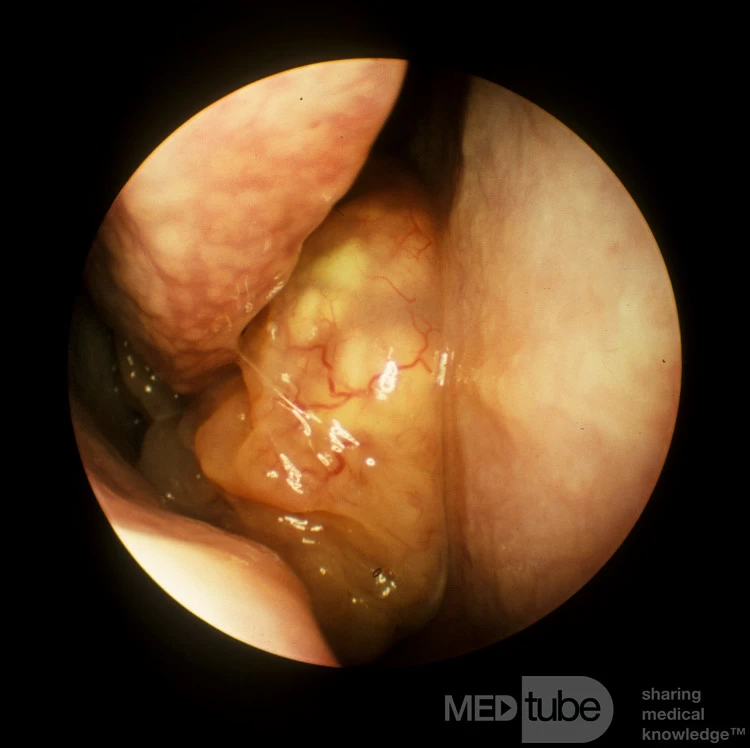

U nhú đảo ngược khoang mũi phải A

Bệnh nhân này có tiền sử tắc nghẽn mũi hai bên. Kiểm tra nội soi phát hiện khối polyp bất thường xuất phát từ cuốn mũi trên bên phải và kéo dài về phía trước vào khoang mũi.